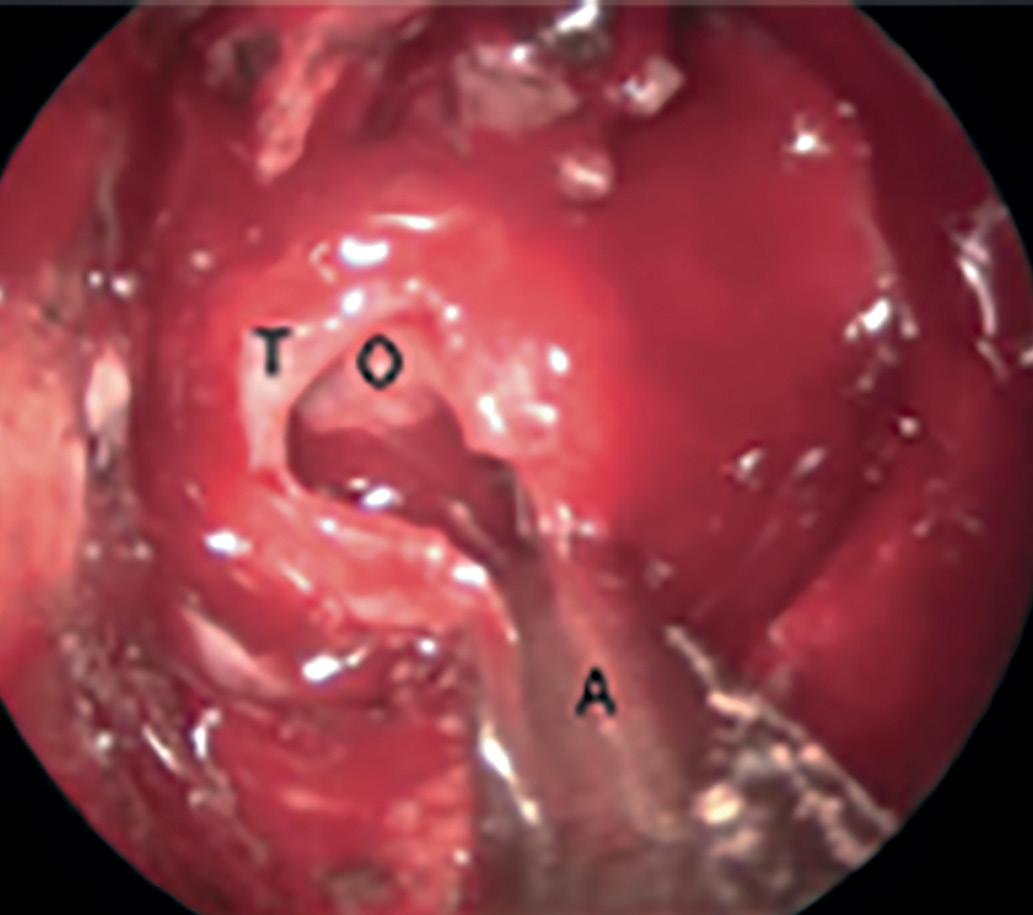

Этапность удаления опухолевой ткани заключается в следующем: удаление начинается с нижней части опухоли, затем латеральных ее частей и в конце производится удаление супраселлярного компонента (при наличии такового) (рис. 4).

Рисунок 4. Процесс удаления опухоли из полости турецкого седла при помощи аспиратора (Т — твердая мозговая оболочка, О — опухоль, А  — аспиратор).